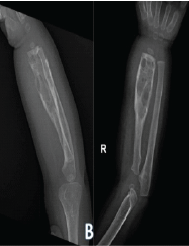

Post-operative Microdiscectomy Complicated by Lumbar Epidural Hematoma with Cauda equina Syndrome Following Dual Viral Infection: A Rare Case Report and Its Management